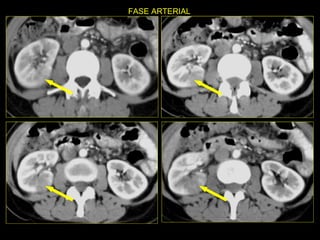

Caso # 4 ♀ , 5ta década de la vida  Presenta dolor abdominal difuso sin poder determinarse la causa clínicamente por lo que se solicita la TC Estudio con cortes axiales y coronales demostrándose  fases arterial y venosa.

FASE ARTERIAL

FASE ARTERIAL FASE VENOSA

Hallazgos Caso #4: Riñón en herradura. Área cuneiforme de disminución de la atenuación en el istmo del riñón en herradura en relación con proceso inflamatorio focal que es exquisitamente demostrada en las RMP coronales.  Lesiones hipodensas, redondeadas en riñón derecho, las cuales no muestran aumento en el valor de atenuación con la ministración del medio de contraste en relación con quistes Bosniak I.